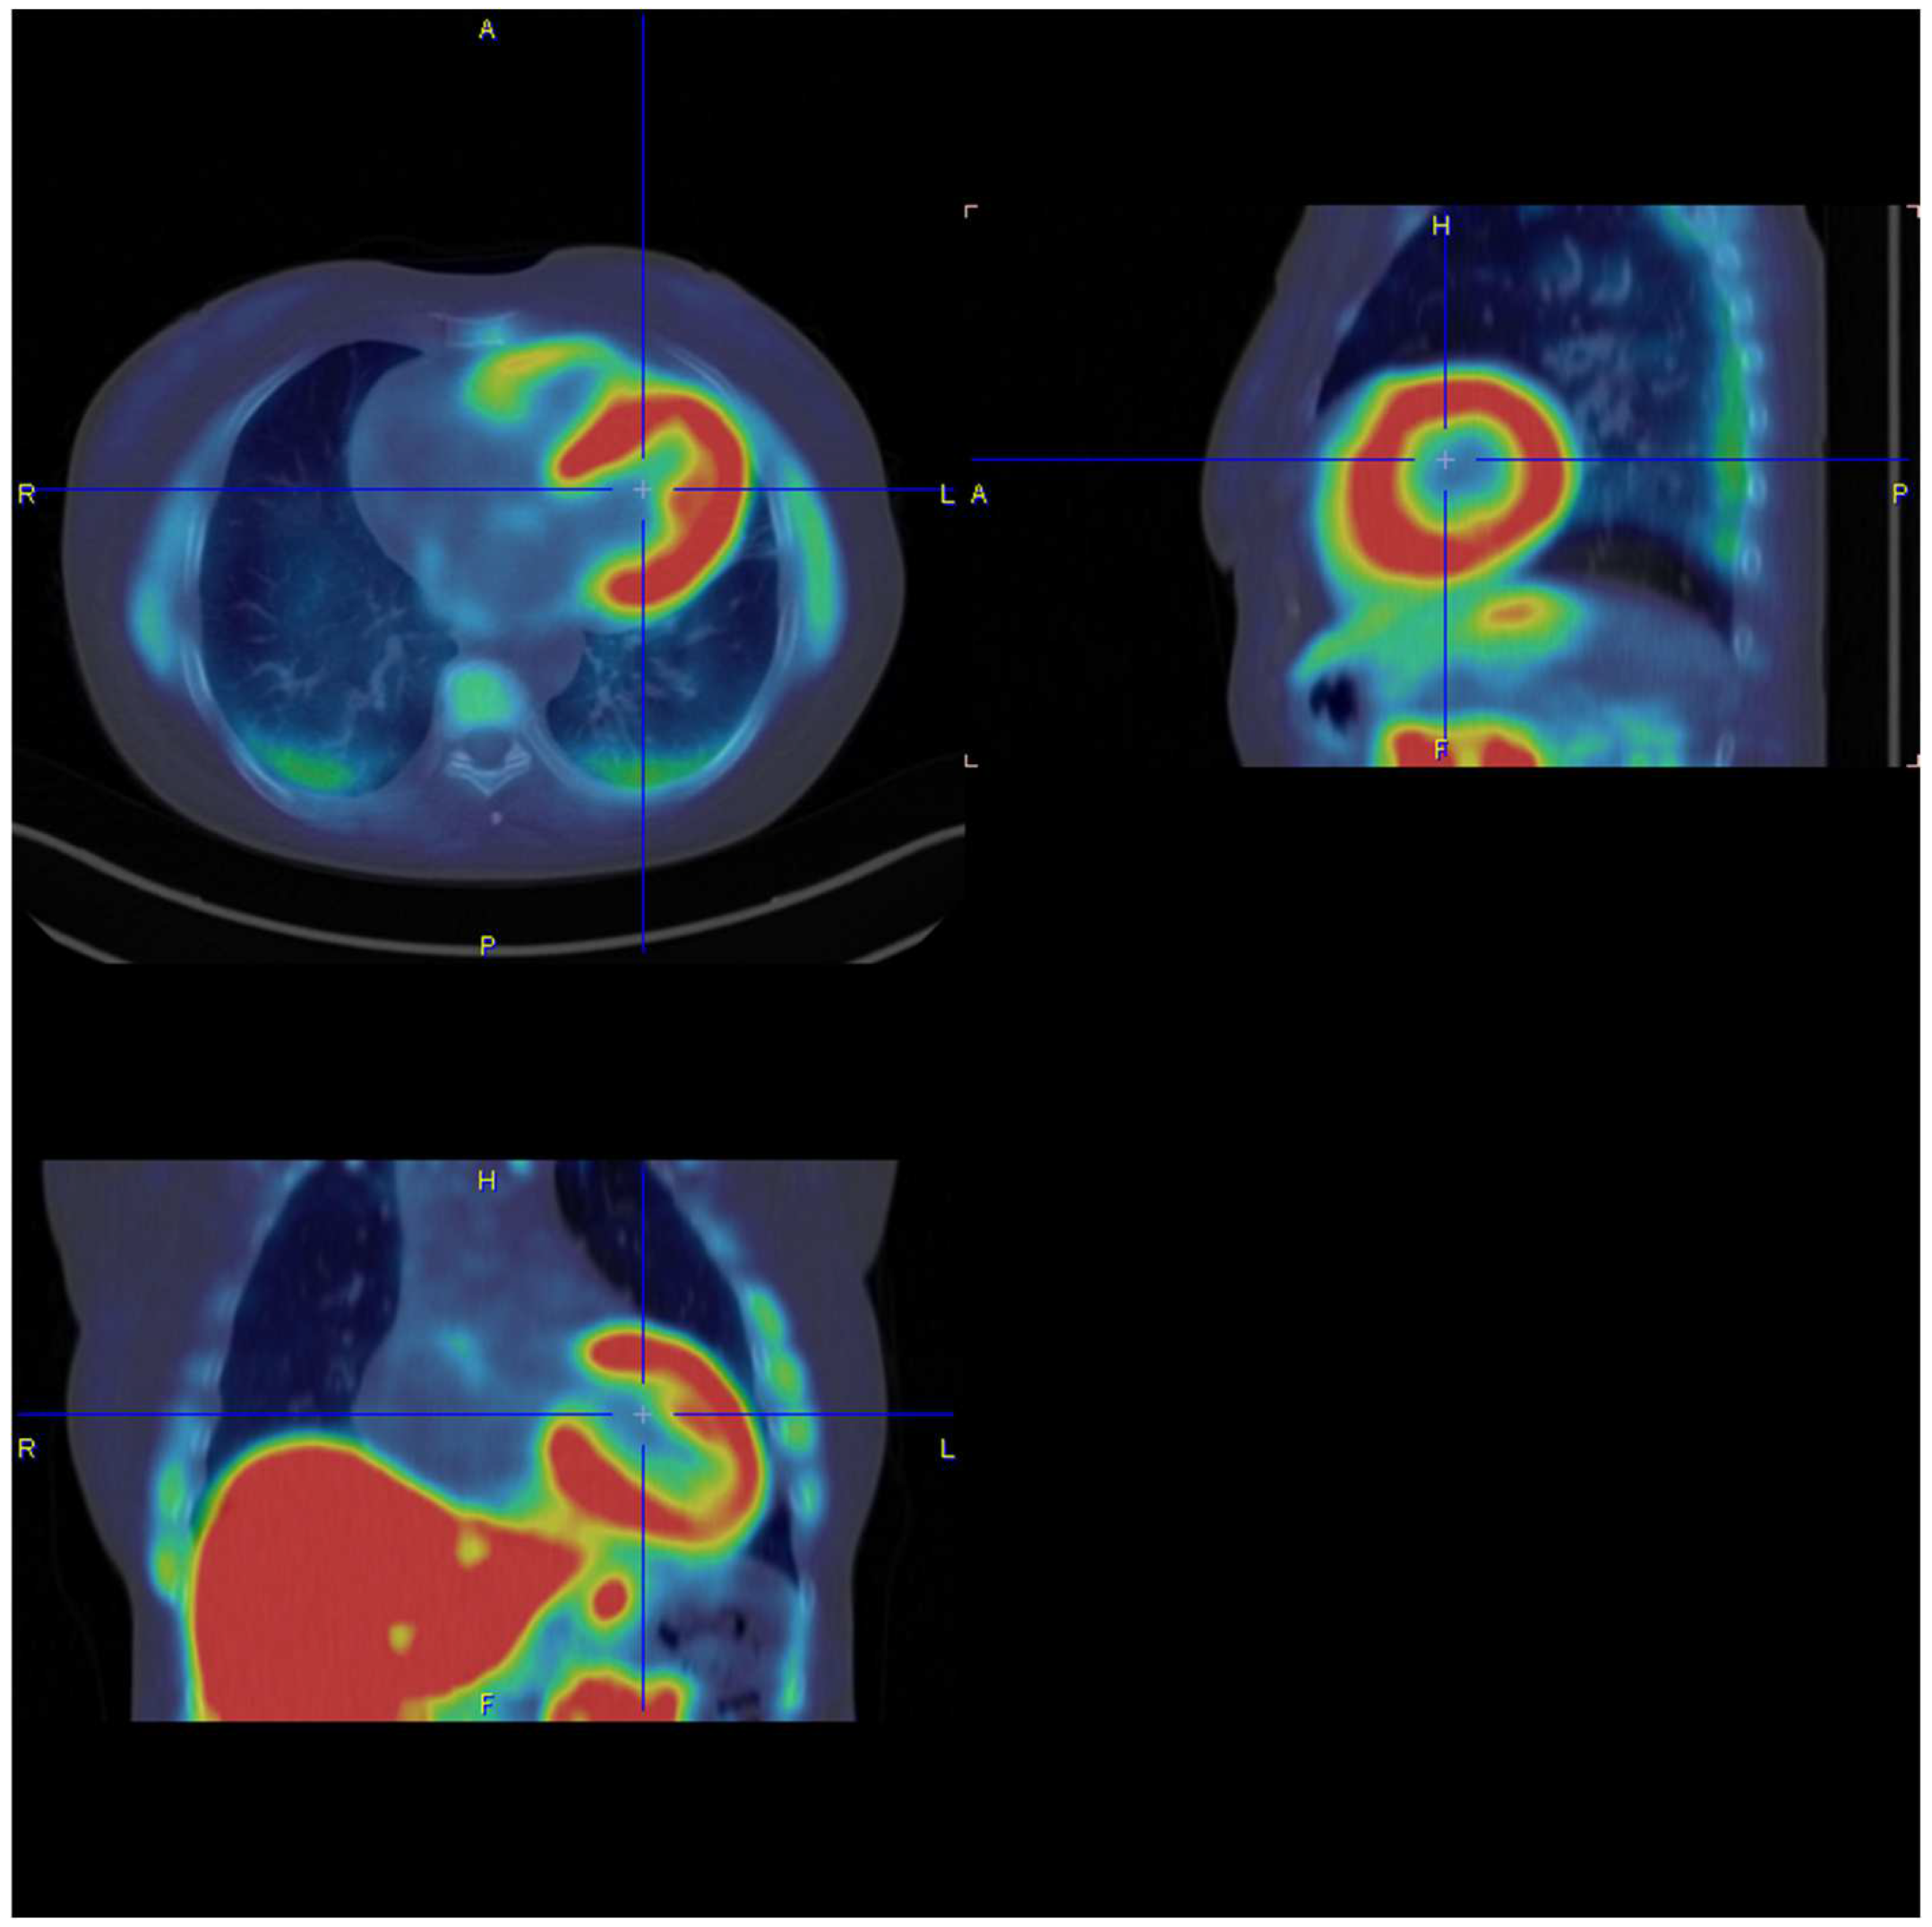

6. Bone Scintigraphy